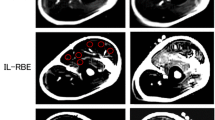

MR images taken from the upper arm of one participant are shown in Fig. 5a. A distinct difference between CON and ECC is seen, such that an increased T2 was found only immediately after CON, but increased T2 was observed for 5 days after ECC. The increase in T2 after ECC was greater for brachialis than biceps brachii and brachioradialis. This is also shown for the averaged results of all participants, as shown in Fig. 6. No significant difference in T2 was found for the baseline between ECC and CON, and between biceps brachii, brachialis, and brachioradialis. A significant interaction effect was found for all muscles, and T2 changed significantly for biceps brachii and brachialis, but not brachioradialis after ECC. T2 of biceps brachii and brachialis increased immediately post-exercise for CON and ECC, but the magnitude of the increase was greater for CON (biceps brachii 34 ± 8 %, brachialis 27 ± 9 %, p < 0.05) than ECC (biceps brachii 18 ± 10 %, brachialis 16 ± 10 %, p < 0.05). T2 returned to baseline by 1-day post-exercise for CON, but was still significantly elevated above baseline for biceps brachii (9–15 %, p < 0.05) and brachialis (17–29 %, p < 0.05) at 1–5 days after ECC.

Changes (mean ± SD) in transverse relaxation time (T2) of biceps brachii (a), brachialis (b), and brachioradialis (c) before (pre), immediate after (0), and 1, 3, and 5 days after concentric (CON) and eccentric (ECC) exercises. *Denotes a significant (p < 0.05) difference between CON and ECC. #Denotes a significant (p < 0.05) difference from pre-exercise value

The present study tested the two hypotheses: (1) the acute T2 change would be smaller after eccentric than concentric exercise and (2) the acute T2 change would be negatively correlated with delayed T2 changes, and the magnitude of changes in muscle damage markers at 1–5 days after eccentric exercise. The results showed that T2 increased greater after CON than ECC immediately after exercise, but returned to baseline by 1-day post-exercise for CON, while T2 was still elevated at 1–5 days after ECC (Figs. 5, 6). The acute T2 change after ECC and the peak T2 change found at 1–5 days after ECC were positively correlated (r = 0.63, Fig. 7a). The magnitude of acute T2 change after ECC showed no correlation with the peak MVC torque, peak CSA, and peak DOMS (Table 1). These results support the first hypothesis, but not the second one.